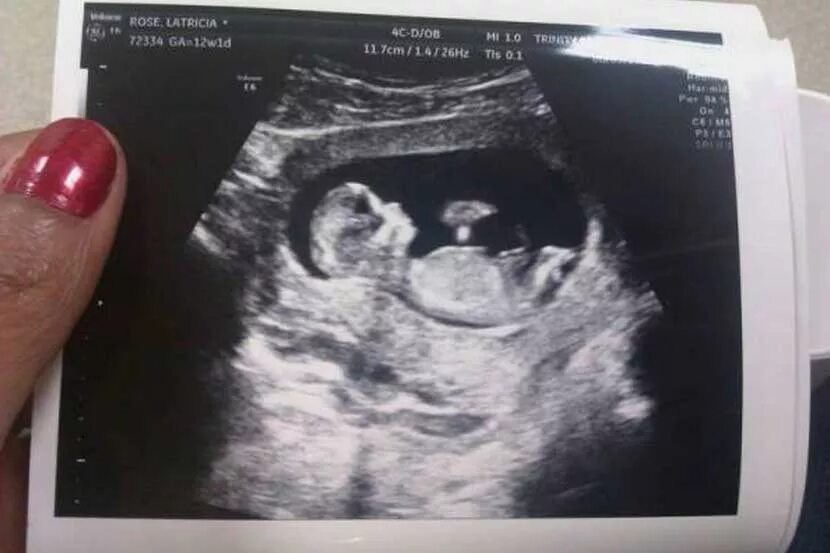

11 недель и 5 дней